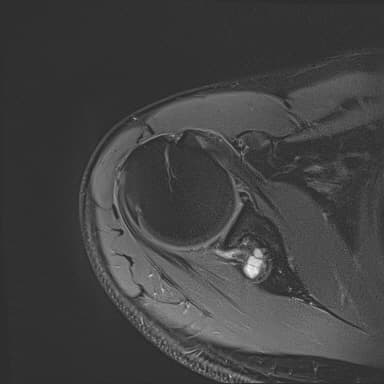

어깨 mri 좀 봐주세요 물혹있다고 하는데 수술해야 하나요?

하도 안 나아서 우측 견관절도 mri 촬영을 했는데 물혹이 있네요